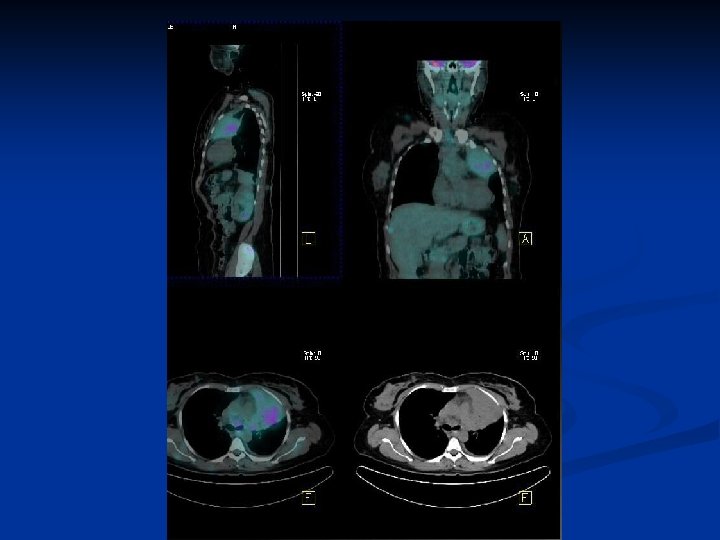

Cas clinique n° 3 (cancer du sein) n n n Femme 66 ans Lombalgies +++ Scintigraphie osseuse douteuse IRM – Réascention CA 15 -3

n Patiente soulagée par chimiothérapie